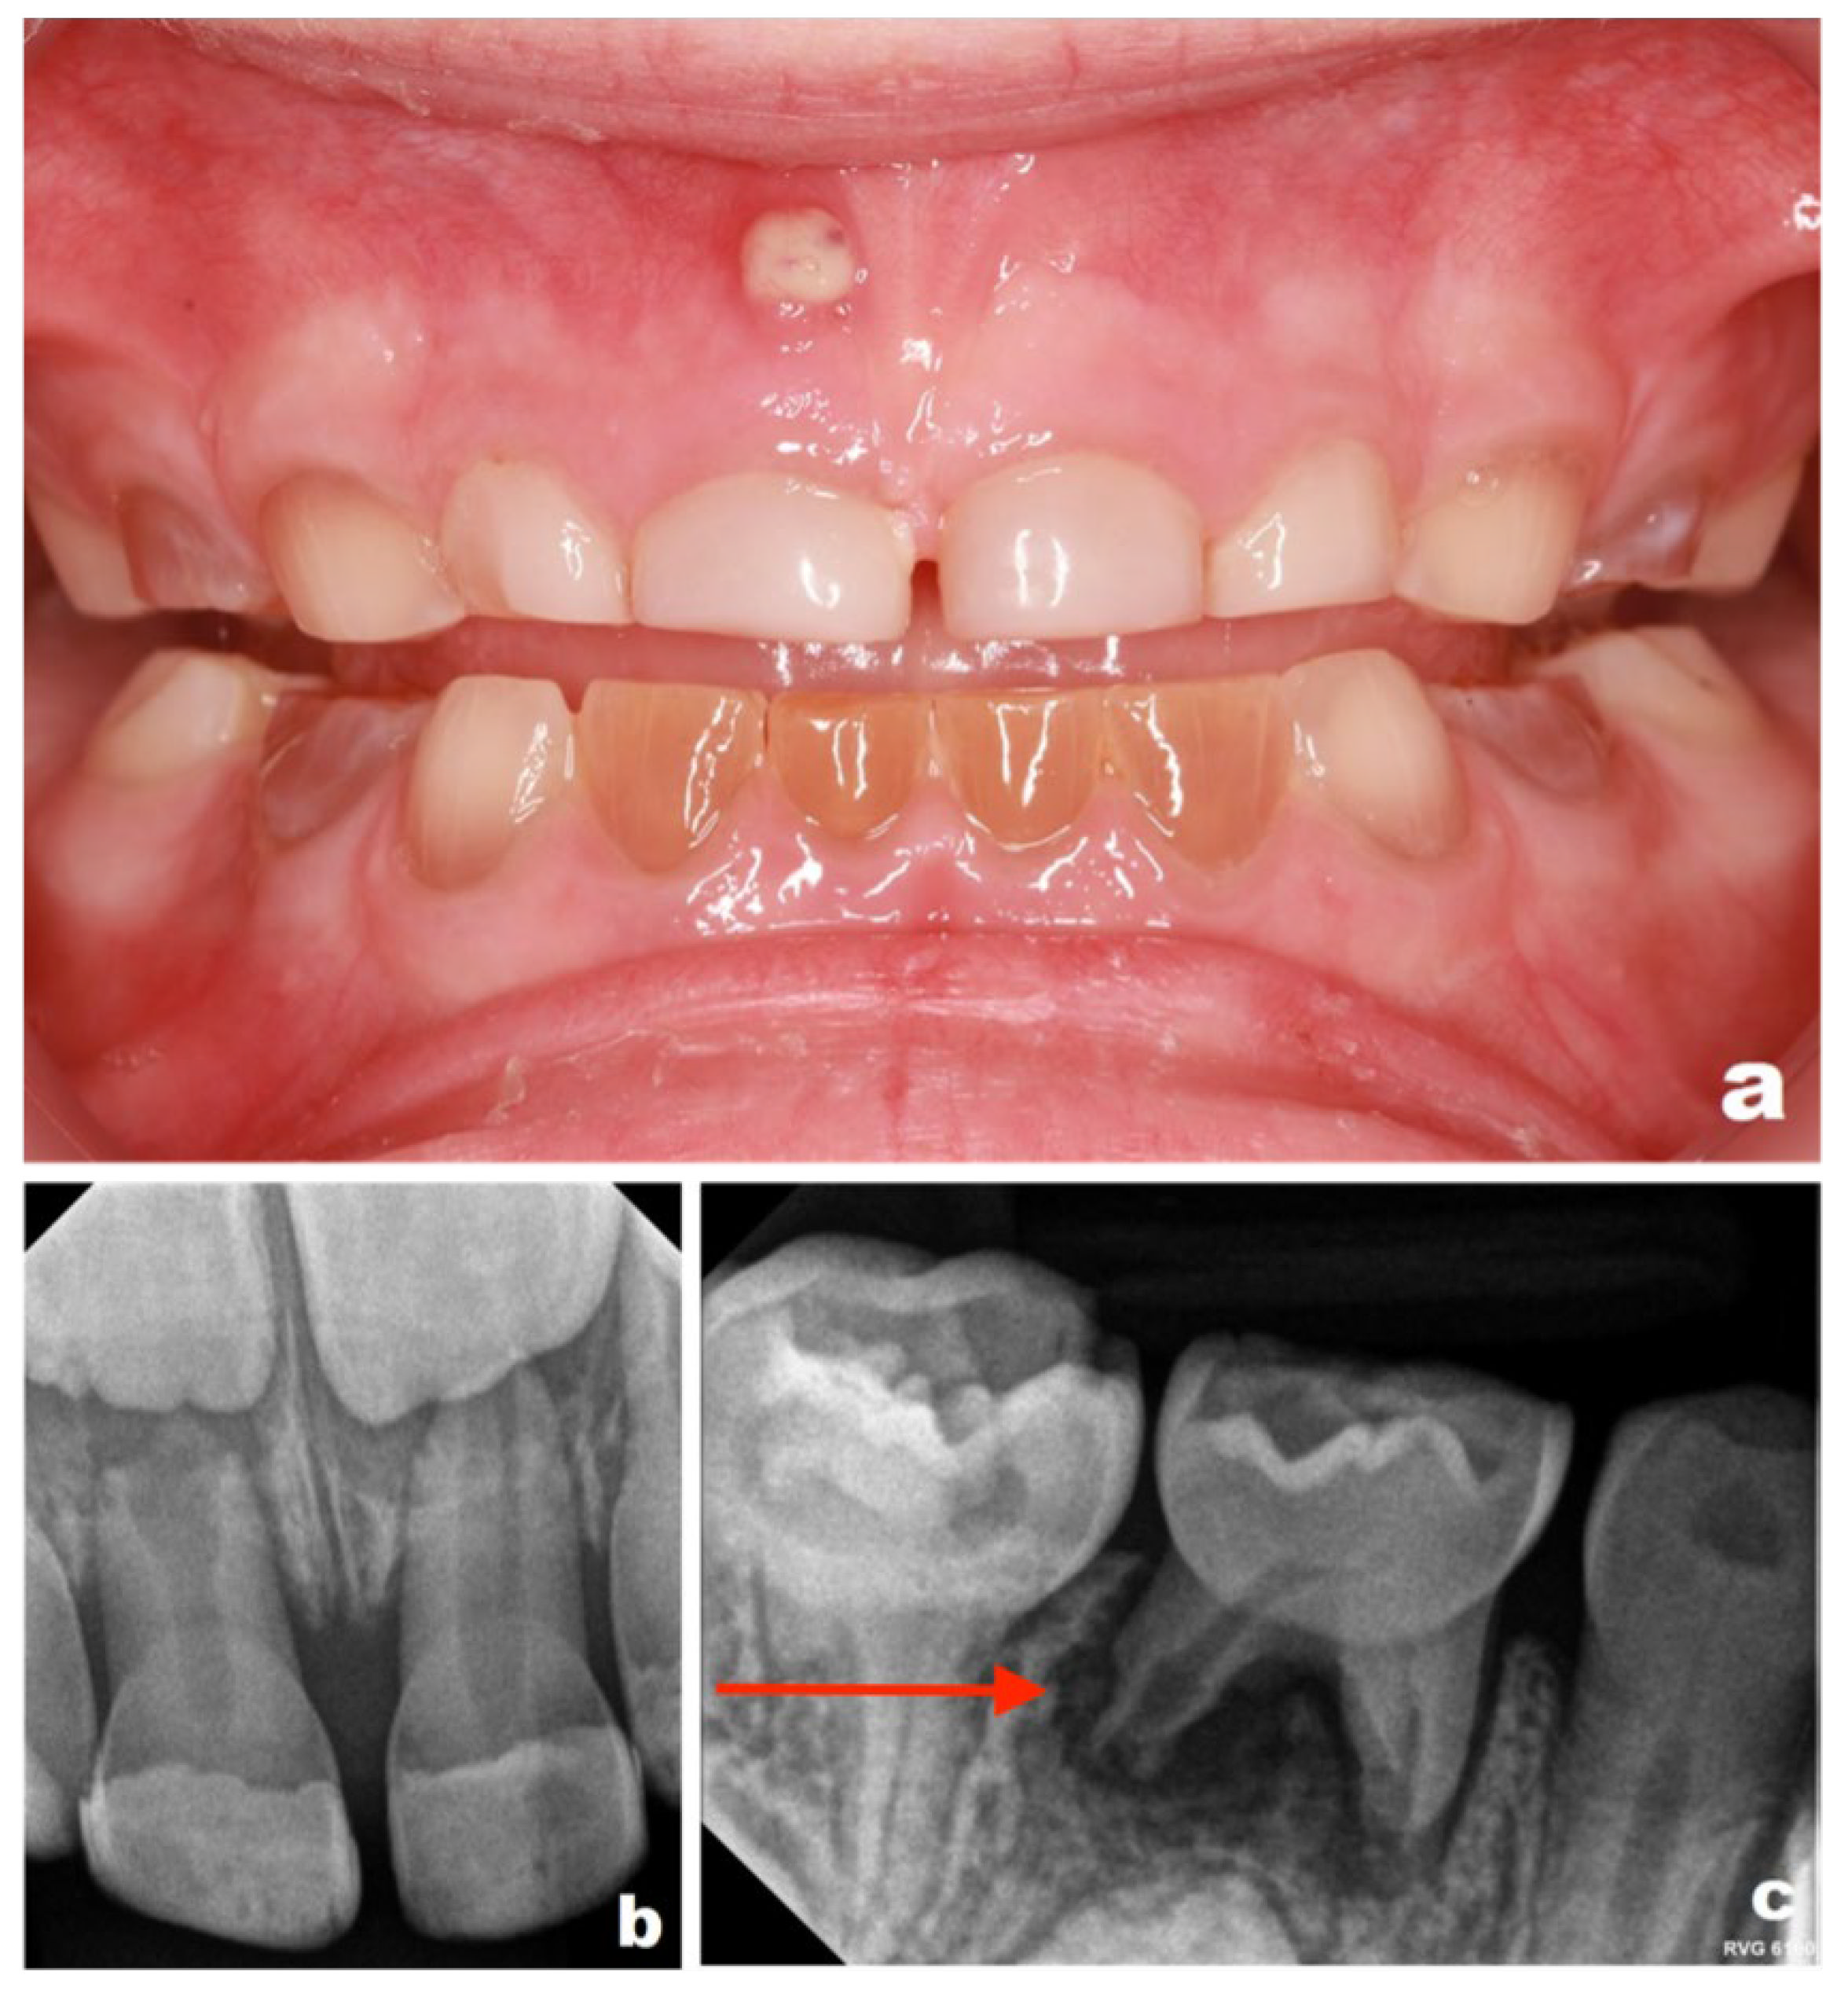

Given the known risk of asymptomatic pulpal and periapical pathology in DI, intraoral photographs and periapical radiographs were obtained in September 2022 (Figure 1a–e) as part of a preventive and diagnostic assessment, despite the absence of acute clinical complaints.

Figure 1. Intraoral photographs obtained in September 2022 (patient aged 3 years), demonstrating generalized discoloration of the primary dentition consistent with DI: (a) anterior teeth in occlusion; (b) upper right quadrant; (c) upper left quadrant; (d) lower right quadrant; (e) lower left quadrant.

Figure 2. Periapical radiographs obtained in September 2022 (patient aged 3 years): (a) maxillary anterior region showing a periapical radiolucency associated with tooth 61 (Please note the area indicated by the red arrow in the figure); (b) upper right quadrant; (c) upper left quadrant; (d) lower right quadrant, demonstrating periapical changes at the distal root of tooth 84 (Please note the area indicated by the red arrow in the figure); (e) lower left quadrant.